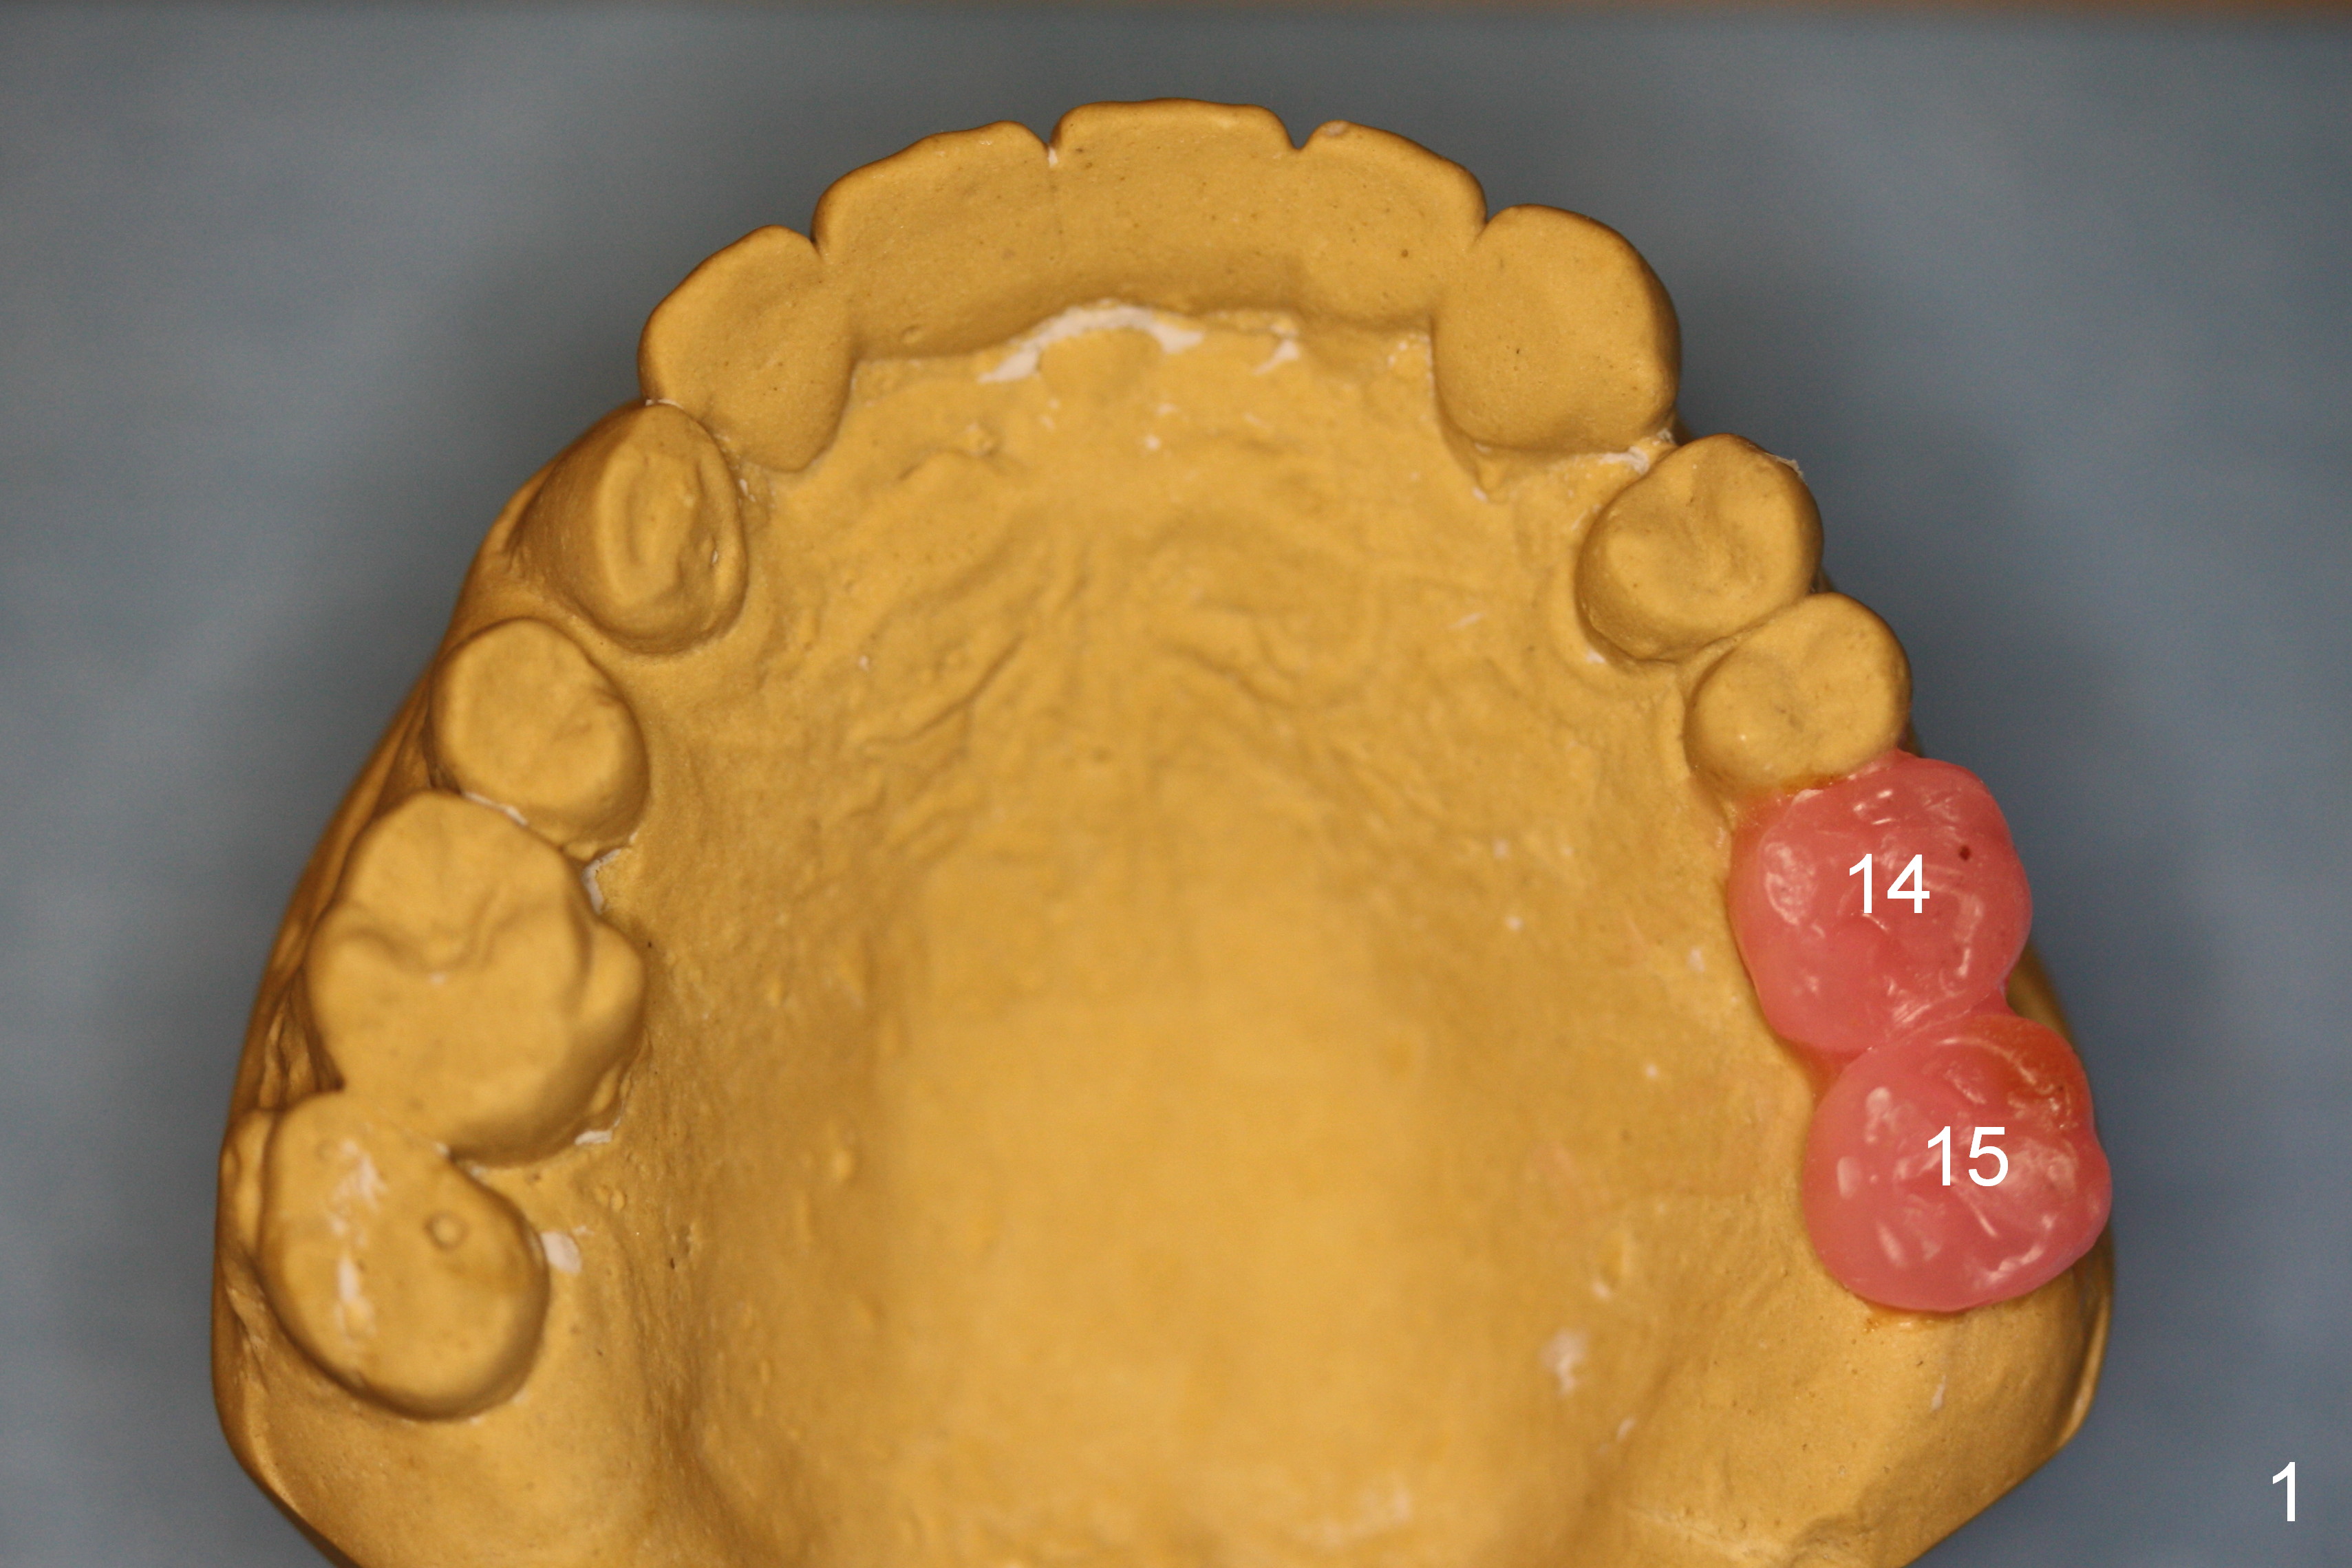

A 52-year-old man has multiple missing teeth. Since he has a lower partial denture (Fig.5), implants will be placed at the sites of #14 and 15 first (Fig.1). The site of #14 may need bone expansion if bone density is low, whereas the ridge at #15 is wide (Fig.2). There is no problem in height at the sites of #14 and 15 (Fig.3).

CBCT confirms that the ridge at #14 is narrower than that at #15. In contrast, the bone density is lower at #15 than that at #14 (Fig.7-9). If the keratinized tissue is wide, use 4 mm tissue punch (3 mm from #13). If incision is made, wheel saws will be used to split the ridge. Or use Magic split and osteotomes. Bone expanders are going to be used for bone expansion at #14 and bone condensation at #15 (Fig.8,9). Be careful while using bone expanders at #14, since the bone density is higher. There is a chance of plate fracture. Use drills if indicated. Fabricate splinted provisional after placement of abutments.